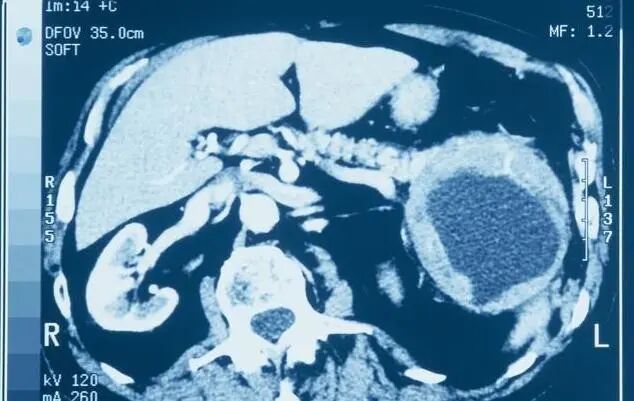

胰腺癌起病隐匿,早期缺乏典型症状、体征,早期诊断困难,大部分患者确诊时已为晚期,治疗困难,已失去了最佳治疗时机,由于侵袭性高,患者预后较差。

目前胰腺癌平均生存时间约6-9个月,总体5年生存率不足10%。手术切除仍是胰腺癌主要治疗手段,但大部分患者因肿瘤侵犯局部重要血管或转移而丧失手术机会,仅不足20%患者可进行手术切除。

综上所述,胰腺癌更青睐于有慢性胰腺炎的人、初发的糖尿病患者、长期吸烟饮酒及生活不规律的人、有家族史的人,而且男性多于女性,老年人更容易患病。因此建议这些高危人群要重视预防,养成良好的生活习惯,并要定期体检,抽血化验、做B超或CT检查,力求做到早发现、早诊断、早治疗。

对于这类人群的筛查,推荐检查手段依次为EUS、 MRI/MRCP、CT、腹部超声、ERCP,必要时可结合胰液分析或者细针穿刺检查。研究发现,绝大多数高危人群胰腺病变表现为囊性病变。目前对于无症状的囊性肿瘤患者建议首选MRI作为随访手段,对于直径小于3cm无症状、无胰管改变、无实性成分的囊性肿瘤患者可1年后复查,若仍无变化则以后可每2年随访1次,若随访5年后该囊性肿瘤仍无变化可终止随访。